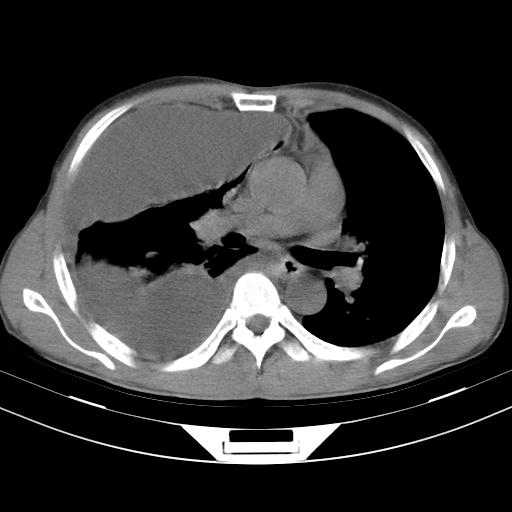

男性,44岁,结核病史多年。现胸闷气短,咳嗽,偶咳血。

右侧胸腔积液

右肺下叶不张

双肺多发结节影最分空洞形成考虑占位不除外结核

1、右侧大量胸腔积液伴右肺压缩性膨胀不全,建议抽液治疗后复查 2、两肺继发性tb伴空洞形成。

1)两肺继发性肺结核伴空洞形成,左肺多发性结核球。2)右侧大量胸腔积液伴右肺部分膨胀不全。3)纵隔淋巴结肿大。